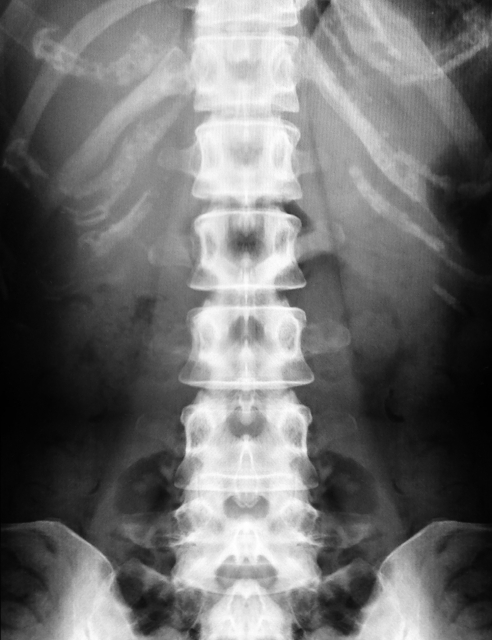

腹部レントゲンでうつるもの

レントゲンは体にX線を当てて、そのX線がどのくらい体を通りやすいかで色合いが変わり、現像されます。

- X線がよく通る=フィルムや検出器にたくさん届く→黒く映る

- X線が通りにくい=フィルムや検出器に届かない→白く映る

- 黒く映る:空気が代表

- 白く映る:骨、人工物(金属)、造影剤(バリウムなど)が代表

- 筋肉や脂肪分など:少しX線を吸収するのでその場所の成分によって、濃淡がつく

おなかの場合

- 骨・バリウムなどの飲んだ造影剤がある、大きな硬い石(胆石など)=白

- 胃、腸の中の空気=黒

- 肝臓や腎臓、筋肉、脂肪など=濃淡のあるグレー

これらが一枚の写真の中にうつっていることになります。

腹部レントゲンの写真からわかること

白くうつるものから

特に造影剤を飲んでいないと仮定すると、白くなっているのは骨です。

背骨と骨盤になります。腹部症状とは大きくは関係ない部位です。